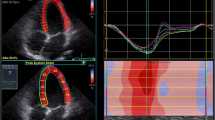

Fig. 1

figure 1

Representative 2-D strain images and strain curves for LV Sl (top) and LV Sc (bottom) at baseline (left, HR = 72 bpm) and during moderate exercise (right, 100 W, HR = 134 bpm)

Exercise stress echocardiography and 2-D strain analysis were performed using the same protocol and by the same internationally accredited operator, as described by our research group previously (Pieles et al. 2015). Briefly, focused echocardiography was performed for 2-D strain analysis during free breathing exercise 60 s into each exercise stage at baseline (rest), 0 (unloaded pedaling), 50, 100, 150 W and during recovery at 2 min (Rec2) and 6 min (Rec6) after end of exercise. The gas exchange threshold (GET), representing the break point in breath-by-breath values of carbon dioxide uptake and oxygen uptake was expressed as a percentage of VO2peak. Myocardial reserve was defined as the difference in 2-D mean peak systolic strain between baseline and each exercise stage to up to 150 W. Strain values were not calculated at work rates higher than 150 W to ensure sufficient image quality and frame rate for reliable strain analysis. Only images with high frame rates of 60–100 Fps were used to ensure capture of sufficient Fps for 2-D strain analysis at higher heart rates. A minimum of 3 cardiac cycles were recorded to capture at least one cardiac cycle in expiration to obtain best image quality, which was confirmed visually and then used to perform strain analysis (Fig. 1).